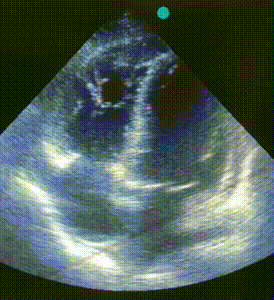

ЕхоКС (7 день):

![]() |

|

A4CH, B-режим. Акінез вільної стінки ПШ і частини МШП, значна дилятація ПШ. |